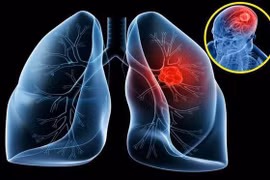

Chỉ khoảng 19% bệnh nhân ung thư phổi nói chung có thời gian sống thêm ≥ 5 năm ở tất cả các giai đoạn được chẩn đoán. Đối với giai đoạn IV, thời gian sống thêm 5 năm rất thấp, chỉ khoảng 2%. Cần biết dự phòng, phát hiện sớm.

56% bệnh nhân ung thư phổi trên thế giới được chẩn đoán ở giai đoạn IV. Tỷ lệ sống còn 5 năm ước tính sau chẩn đoán ung thư phổi giai đoạn cuối chỉ 6.3%. Vì vậy, cần nhận biết để phát hiện sớm.

Trong nỗ lực ngừa ung thư phổi, từ bỏ thói quen hút thuốc lá là một trong những yếu tố không thể thiếu. Ngoài ra, bạn có thể tăng khả năng ngăn ngừa ung thư phổi bằng việc thường xuyên ăn những thực phẩm dưới đây.